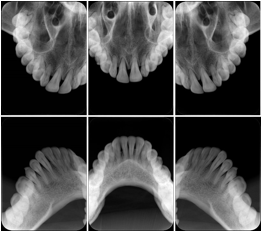

2. A patient requests cosmetic surgery to enhance their facial appearance. The case requires consultation between an orthodontist in New York and an oral surgeon in California. The cephalometric series of 2D projections constructed from the volumetric CT data that is used for the discussion is arranged by a Structured Display for transfer between the two practitioners.

Cephalometric Series Structured Display

Figure OO-2. Cephalometric Series Structured Display

3. A dental provider wishes to capture a series of DICOM IO images for the patient’s dentition. The tooth morphology, teeth are divided into molars, premolars, canines and incisors, and a number of images for each jaw. The anatomic information was captured utilizing the triplet of schema. This standard code sequence is based on ISO 3950-2010, Dentistry - Designation system for teeth and areas of the oral cavity.

Every IO image should have anatomic information either through the primary or modifier sequence.

In most standard cases, images are oriented in structured layouts. These structured displays are useful to be shared between providers for reference purposes.

Table OO.1.1-1 shows structured display standard templates, where Viewset ID is based on the Japanese Society for Oral and Maxillofacial Radiology (JSOMR) classification provided by JIRA (Japan Medical Imaging and Radiological Systems Industries Association, www.jira-net.or.jp). Expected or typical teeth to be imaged location, region and designation codes are based on ISO 3950-2010, Dentistry - Designation system for teeth and areas of the oral cavity. For all the hanging protocols listed in OO.1.1-1, the value to use for Hanging Protocol Creator (0072,0008) is "JSOMR" and the value to use for Hanging Protocol Name (0072,0002) does not include "JSOMR" (e.g., "DL-S001A", not "JSOMR DL-S001A").